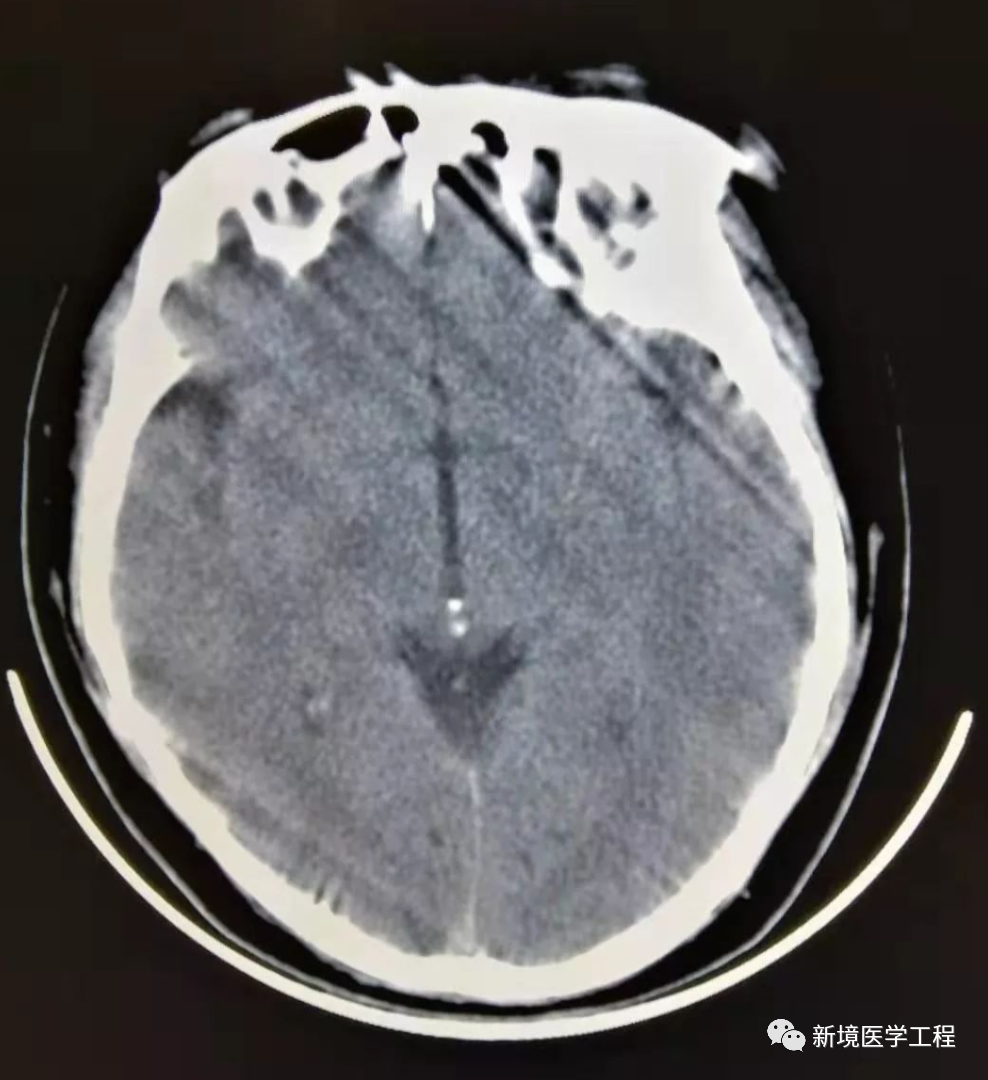

2.1「头部运动伪影」

【产生原因】

患者在时头部运动导致。

【解决办法】

-

重新并确保患者保持不动。

-

采取螺旋方式

-

采用420度

-

利用附属装置(如楔形头侧垫)固定头部